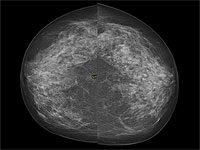

В Европе от донора спермы с генной мутацией, приводящей к раку, были зачаты 200 детей

Донор спермы с генной мутацией, радикально повышающей риск развития рака, стал отцом 200 детей по всей Европе. Это выяснилось в ходе масштабного расследования, проведенного крупными вещателями, включая CBS News, BBC News.